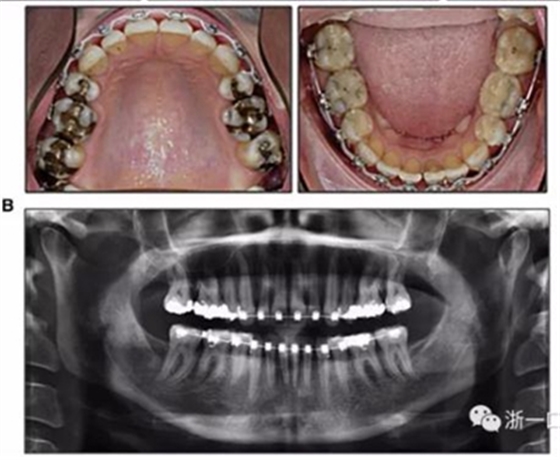

由于下頜中切牙間沒(méi)有間隙行下頜正中切開(kāi)術(shù),故進(jìn)行術(shù)前正畸擴(kuò)展間隙。下頜前牙粘托槽,中切牙托槽成交放置,將中切牙牙根分開(kāi)。使用0.018X0.018鎳鈦絲及置于下頜左、右中切牙之間的推簧推間隙。3個(gè)月后拍攝CBCT示已有足夠間隙行下頜正中截骨術(shù)。

手術(shù)前三周,上、下頜磨牙和前磨牙使用分壓圈進(jìn)行分牙。術(shù)前一天,去除下頜切牙托槽,安裝hyrax擴(kuò)弓器。

全麻下進(jìn)行上頜骨腭中縫骨皮質(zhì)劈開(kāi)及下頜正中劈開(kāi)術(shù)。手術(shù)后,用X光片檢查上頜骨和下頜骨中線切口的位置和方向。

術(shù)后第9天開(kāi)始旋轉(zhuǎn)擴(kuò)弓器,每天轉(zhuǎn)2次,每次轉(zhuǎn)90度,即擴(kuò)開(kāi)0.5mm。每隔1周進(jìn)行檢查,目標(biāo)上頜擴(kuò)開(kāi)9mm,下頜擴(kuò)開(kāi)6mm。18天后,上頜中切牙間出現(xiàn)8mm間隙。下頜出現(xiàn)6mm間隙,(于13天出現(xiàn)后,停止旋轉(zhuǎn)擴(kuò)弓器)。在擴(kuò)弓器旋轉(zhuǎn)3天后,拍片發(fā)現(xiàn)左下頜中切牙遠(yuǎn)中牙根中段有一條低密度陰影,臨床冷熱診反應(yīng)遲鈍,可能為術(shù)中損傷所致。牙體牙髓科會(huì)診,建議行根管治療,故行根管治療。

擴(kuò)弓保持8周后,除擴(kuò)弓器影響牙外粘接托槽,使用0.014鎳鈦絲進(jìn)行排齊、整平。旋轉(zhuǎn)停止后3個(gè)月拆除擴(kuò)弓器,全口粘接托槽,使用0.016niti繼續(xù)排齊整平。佩戴可摘保持器,保持上頜寬度。在使用至0.018x0.018niti7周,徹底排齊整平后,使用大弓型的0.016x0.022不銹鋼絲,繼續(xù)維持原有寬度,同時(shí)停止使用可摘保持器。掛II類(lèi)牽,糾正磨牙關(guān)系,使用鏈圈關(guān)閉散在間隙,少量使用IPR去除局部前牙的黑三角。術(shù)后9個(gè)月拍全景示,牙根平行度可,再無(wú)其他牙根出現(xiàn)問(wèn)題。1年7個(gè)月后治療結(jié)束。上下頜3-3舌側(cè)保持器+哈雷氏保持器進(jìn)行保持。